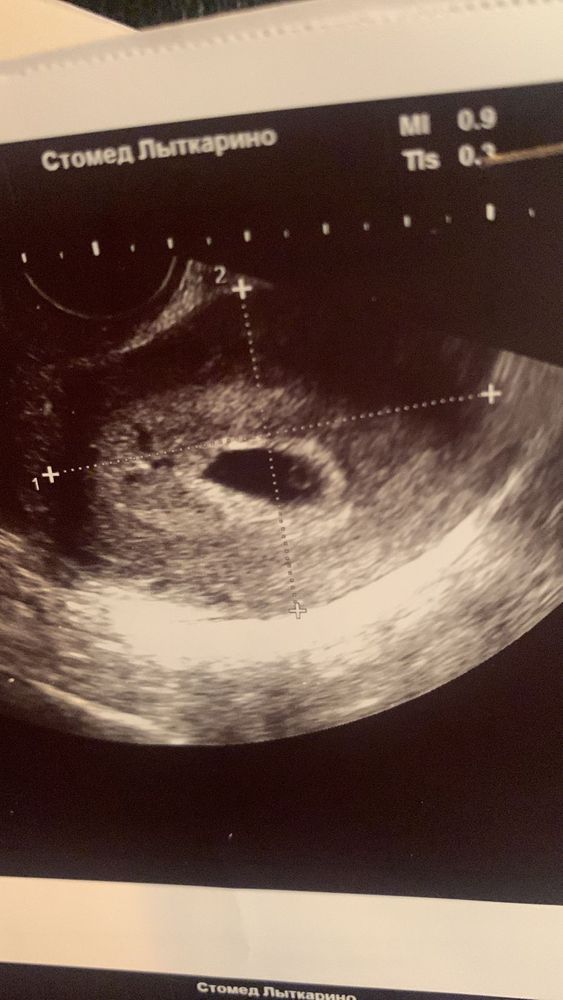

На сроке 5+5 сделали УЗИ, нашли пложное яйцо 15мм и ЖМ -3.3 мм, а вот эмбриона даже намека нет. Девочки, у кого как было, поделитесь

На сроке 5+5 сделали УЗИ, нашли пложное яйцо 15мм и ЖМ -3.3 мм, а вот эмбриона даже намека нет. Девочки, у кого как было, поделитесь